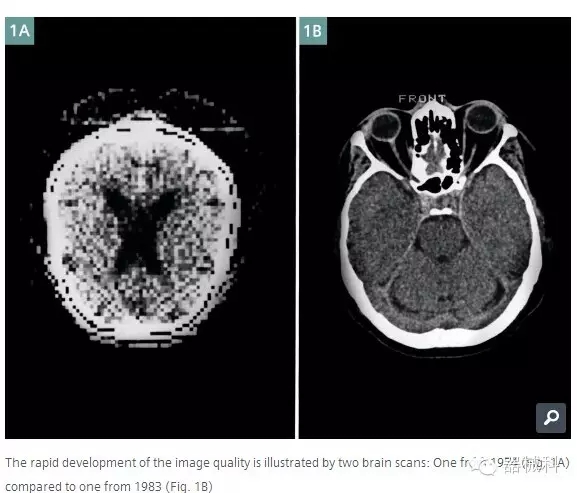

1974年的腦部圖像到了1983年圖像清晰度已經(jīng)有了本質的提升